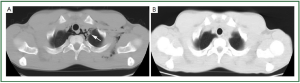

Following four days, the patient presented again at our unit for complaint of persistent chest pain and dyspnea which presented again after coughing. Radiological evaluation diagnosed the presence of pneumomediastinum (Figure 2A). All laboratory and diagnostic tests were within normal. Yet, the patient underwent bronchial hyperreactivity test which resulted as negative Thus, he was managed as before and discharged after 7 days. CT scan diagnosed the complete resolution of pneumomediastinum without sequel (Figure 2B).

Figure 2. Presence of emphysema within superior mediastinum, around the trachea (A), and its complete reassorbation 7 days after (B).